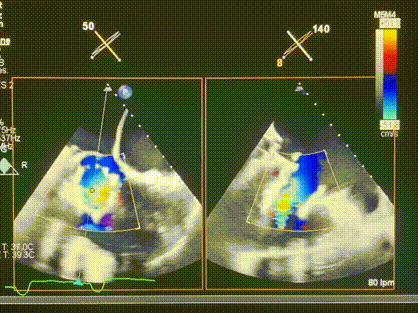

術(shù)中輸送器在超聲引導(dǎo)下調(diào)整位置

手術(shù)在全麻狀態(tài)下進行。術(shù)者采用經(jīng)右側(cè)頸靜脈入路的方式將輸送器送入患者心臟內(nèi),在TEE及DSA引導(dǎo)下調(diào)整輸送器頭端角度,使得輸送器與三尖瓣瓣環(huán)平面垂直。在輸送器進入右心室后釋放室間隔錨定裝置,而后釋放瓣葉夾持件(2個耳片結(jié)構(gòu))成垂直狀態(tài)。在TEE及DSA確定夾持件固定至三尖瓣葉根部且位于右室側(cè)后釋放人工瓣心房側(cè)盤片。隨后調(diào)整瓣膜同軸性以及室間隔錨定件位置(貼合室間隔),前推藏針管并固定,進而釋放室間隔錨定裝置,并再次確認瓣膜位置、穩(wěn)定性及同軸性,合攏輸送鞘后撤出輸送器,完成LuX-Valve Plus人工三尖瓣瓣膜的植入,僅殘余微量瓣周漏。且經(jīng)手術(shù)中心電生理團隊評估,病人的起搏器和ICD功能沒有受到影響。

術(shù)后超聲顯示僅殘余微量瓣周漏